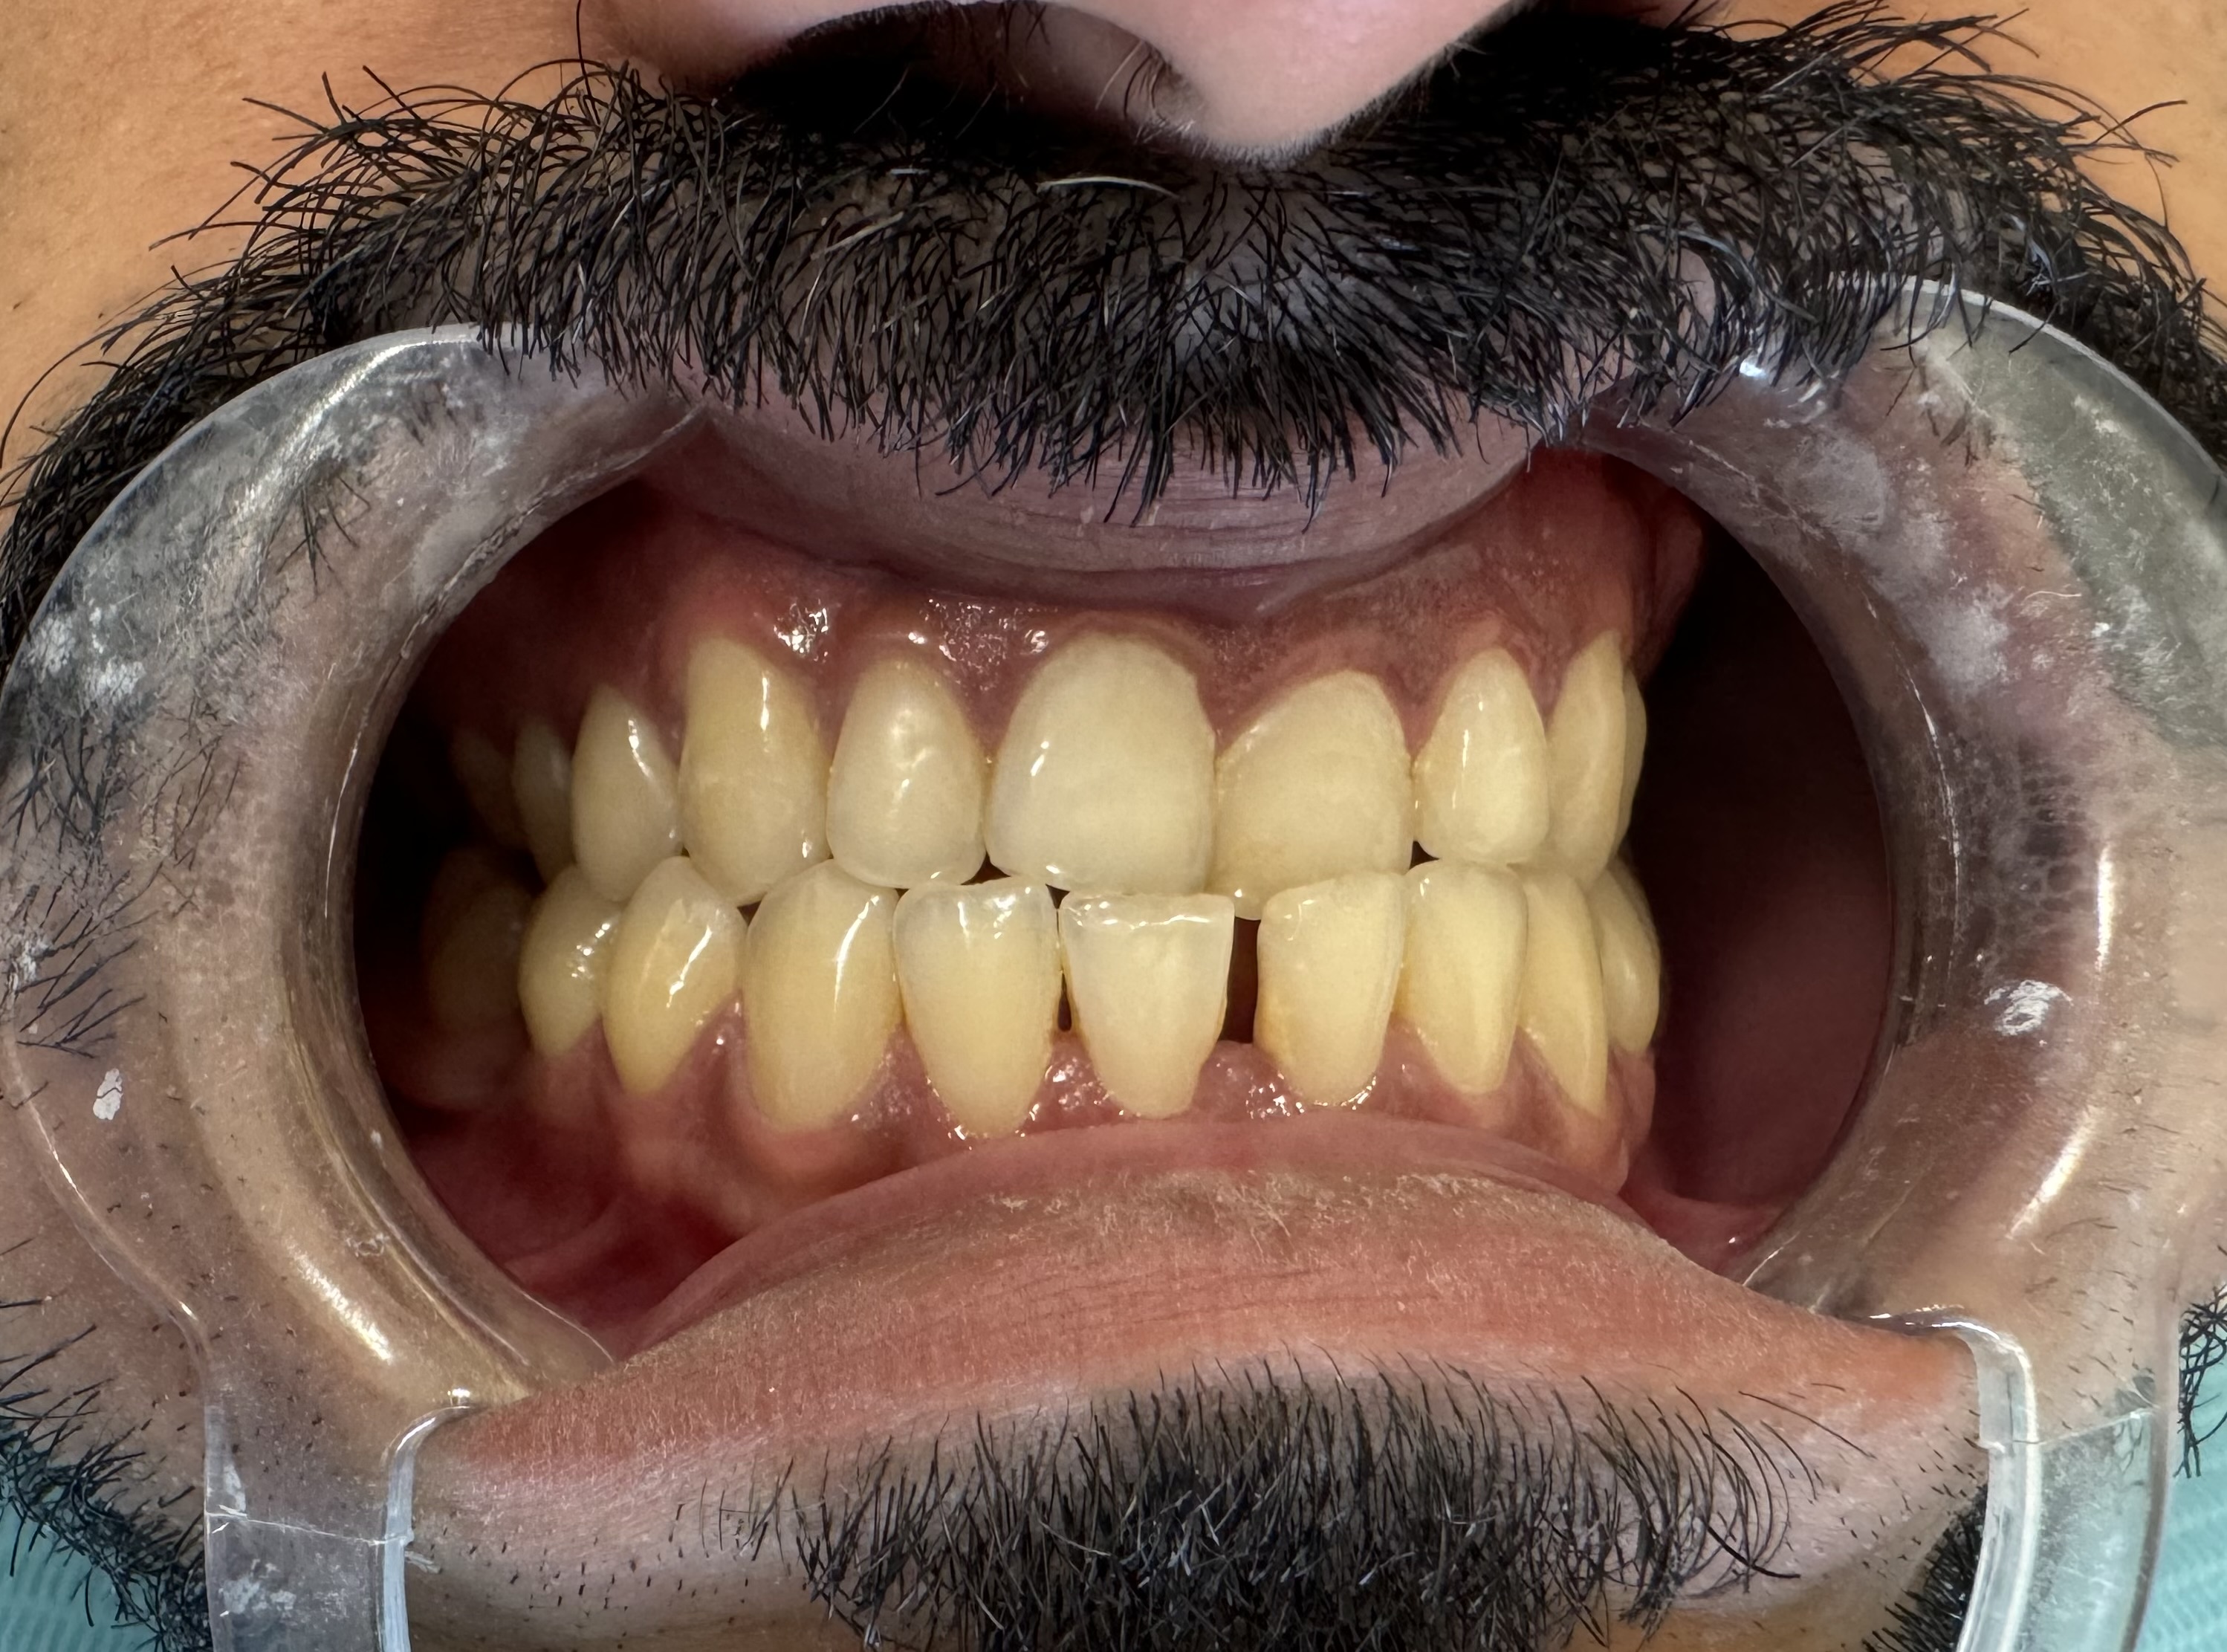

Before